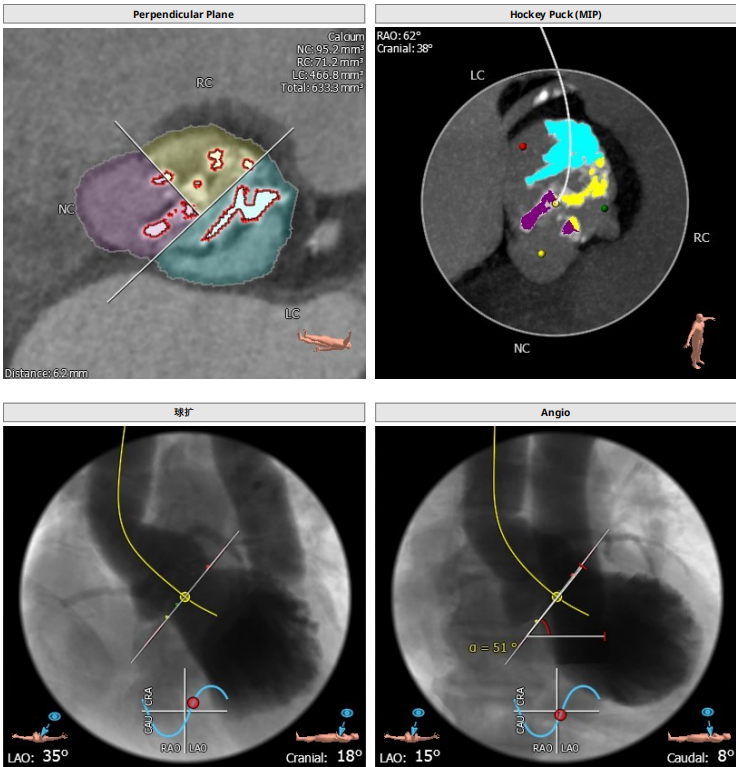

解剖上,这个患者虽然是右无融合的二叶瓣,但是右窦发育较小,形态上接近0型二叶瓣,瓣上钙化中,且集中在左窦,接近左右瓣叶联合部。瓣环及流出道平面较大,而瓣上结构较小,瓣叶联合部距离只有26,这种情况下只能考虑根据瓣上结构进行选择瓣膜。目标瓣膜为26号,为了避免破坏瓣上结构,我们选择26瓣膜的下限20号瓣膜进行与扩张。因为主动脉弓和升主动脉角度问题,没有选择plus。20球囊扩张可以看到左窦钙化很硬,右无联合可以推开,没有反流,故选择26号瓣膜,高位释放。释放后瓣膜下滑到标准位,有明显的腰,故用20球囊进行后扩展。最后造影虽然有中度瓣周漏,但是考虑患者狭窄解除,且升主动脉人工血管限制了瓣膜的流出端,未再行瓣中瓣。术中撤除ECMO,辅助循环约1小时。

患者既往行全升主人工血管置换,为type1型二叶瓣畸形患者,瓣环28.7,左室流出道30.2,二叶瓣鱼嘴短径为26.6,重度钙化,左右冠分别为12.7与15.1,STJ30.8,升主均径人工血管为27.7,患者EF值极低,心功能极差,遂行ECMO辅助下TAVR术式。

根部解剖: